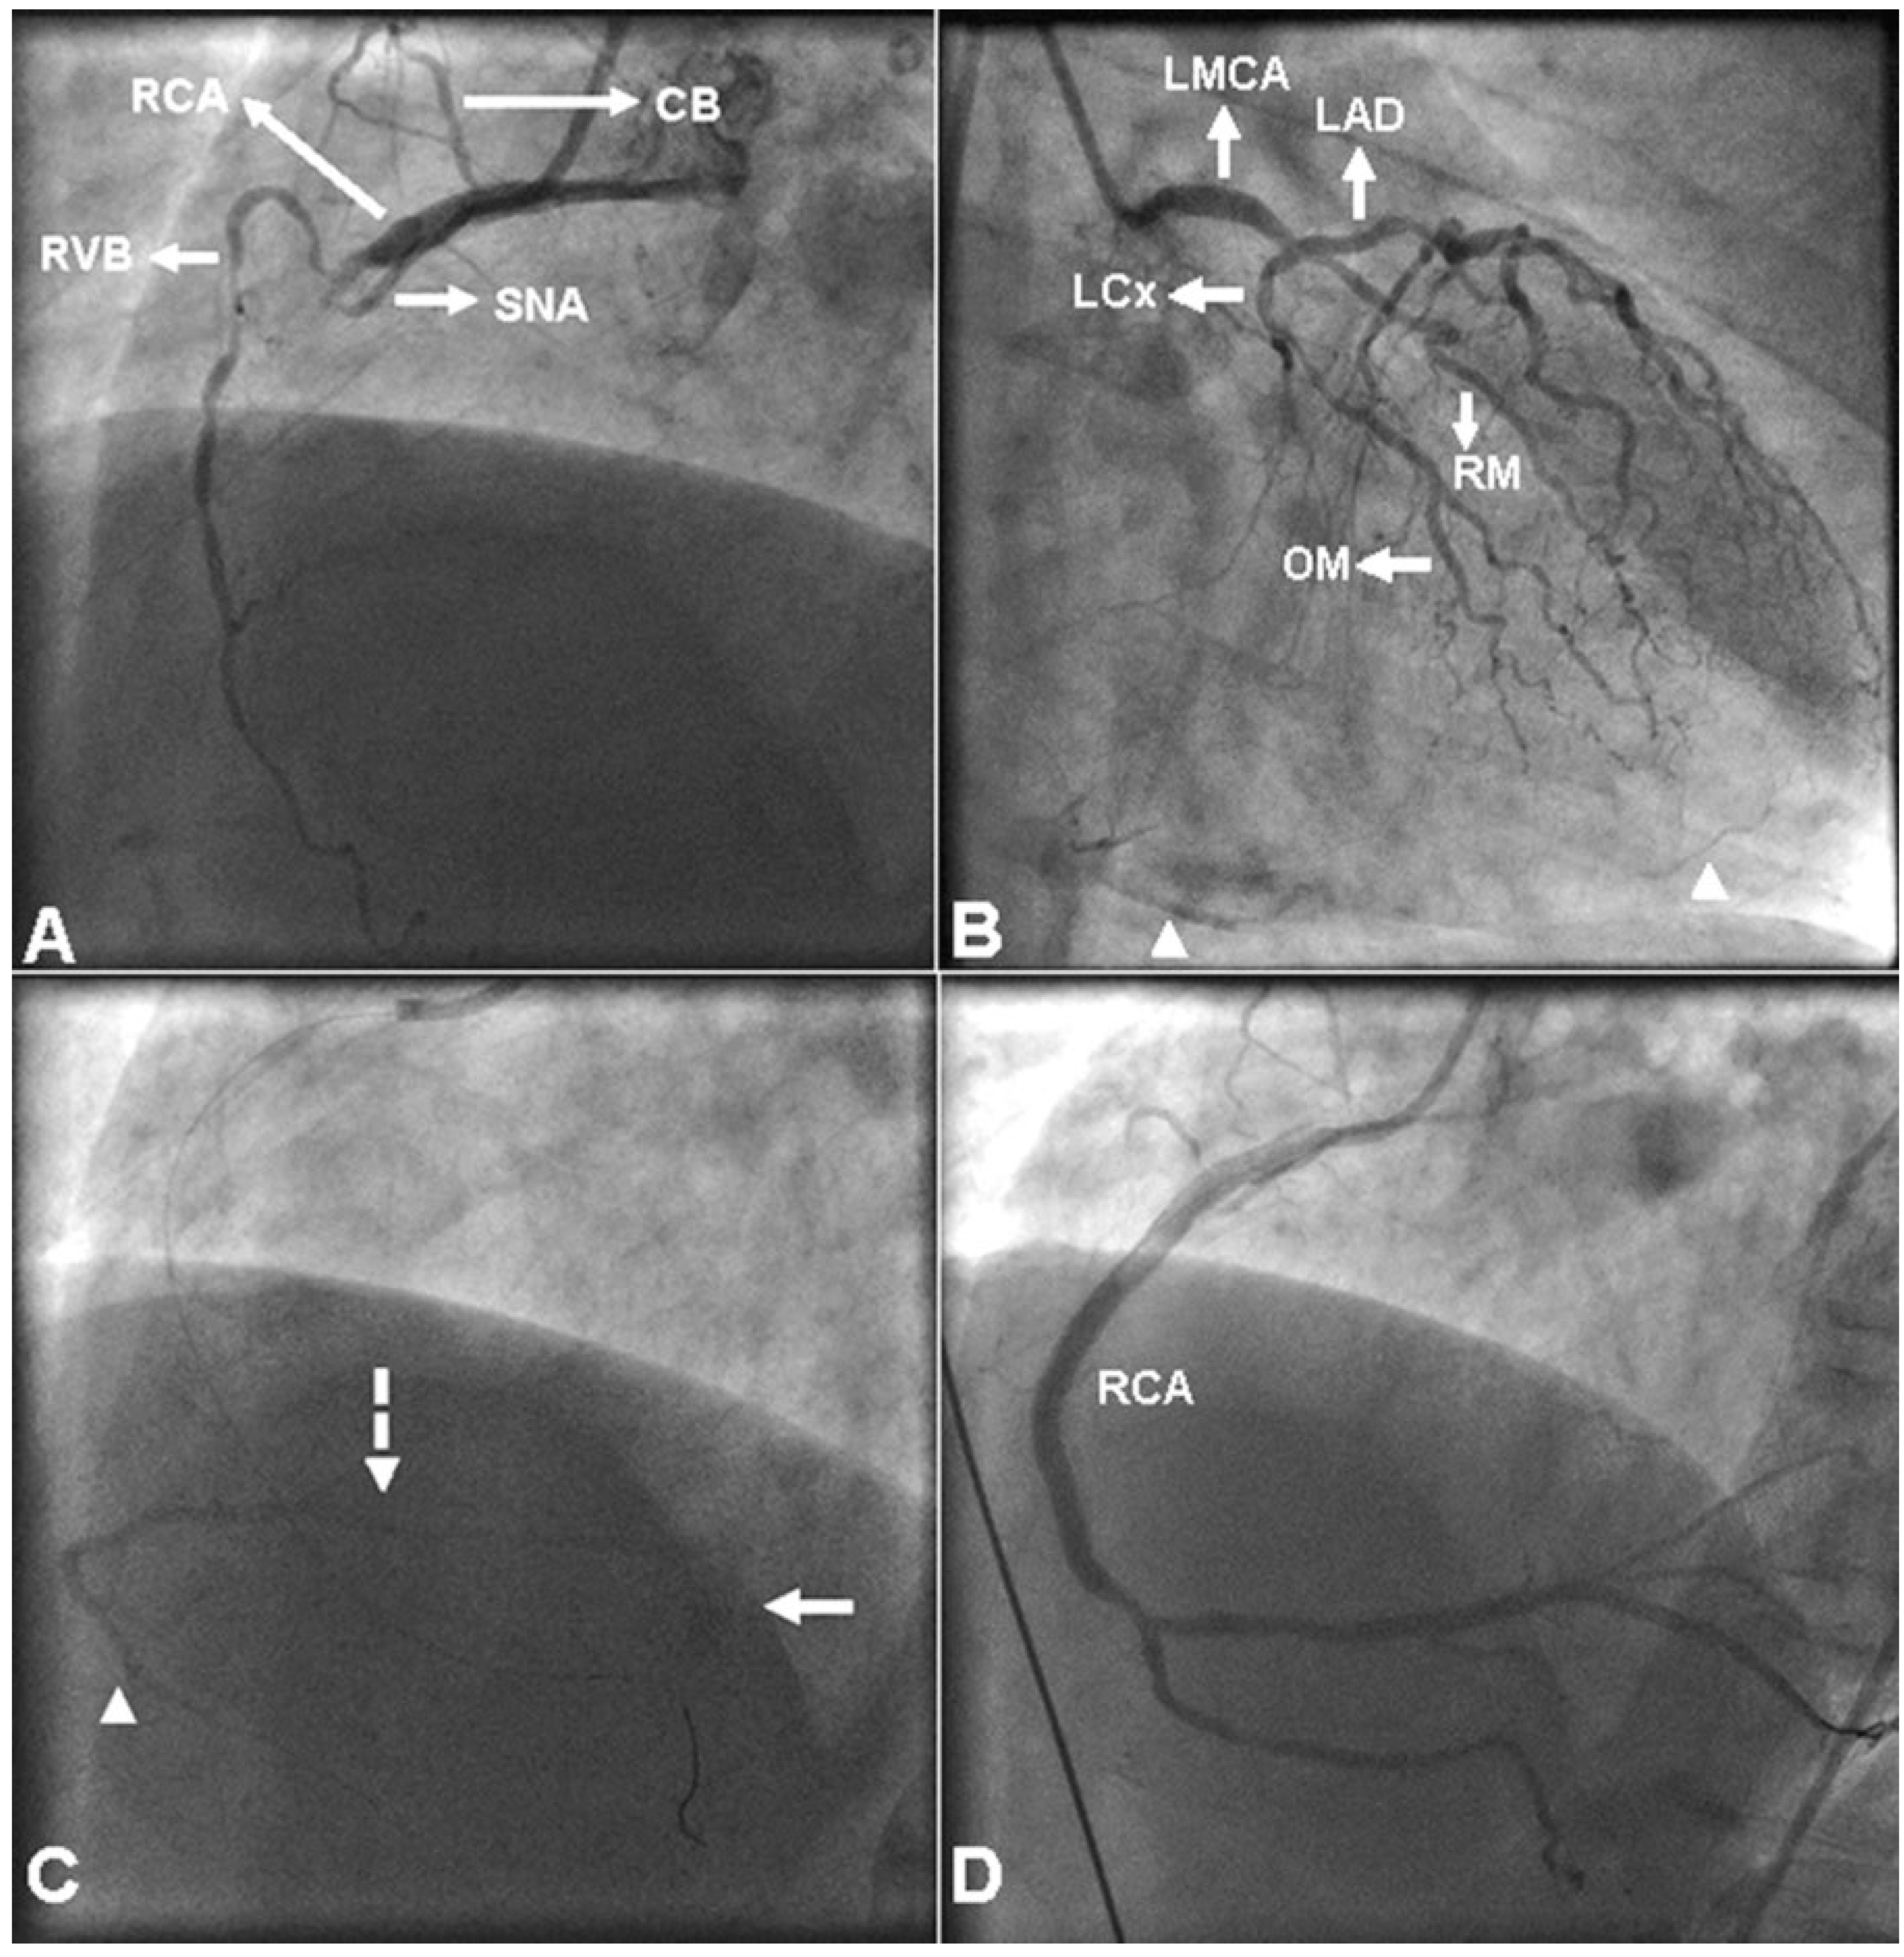

A 66-year-old man presented with substernal chest pain of one hour’s duration and electrocardiographic evidence of acute inferior wall ST-segment elevation myocardial infarction. He underwent emergency coronary angiography that showed total occlusion of the mid right coronary artery (RCA) (Figure 1A) just beyond the origins of a right ventricular branch (RVB) and the sinus node artery (SNA), and significantly obstructive lesions in the distal left main coronary artery, the proximal left anterior descending artery and the obtuse marginal artery. Collateral circulation (Rentrop grade II) to the distal RCA branches from the left coronary artery was also noted (Figure 1B). Initial angiography of the RCA also showed a peculiar, faintly visualised vessel in an area corresponding to the acute margin of the heart, which was initially assumed to be the distal RCA being collateralised from the RVB (moving image 1) (You will find the videos the website www. cardiovascmed.ch in the section «Online only».). During subsequent percutaneous coronary intervention, the guide wire tracked up the distal RCA outside the faintly visualised vessel, which was seen as comprising two branches and a drain point (Figure 1C; moving image 2 and moving image 3); it was thus recognised as a coronary vein. Percutaneous coronary intervention was completed with delivery of three bare-metal stents across the mid RCA lesion and two bare-metal stents across a lesion from the distal RCA to posterior left ventricular branch. Final RCA angiography disclosed Thrombolysis in Myocardial Infarction (TIMI) grade III flow, occlusion of the RVB, subocclusion of the SNA and disappearance of the previously seen coronary vein (Figure 1D and moving image 4). The patient had an uneventful hospital course and was referred for surgical revascularisation of the left coronary artery lesions.

Figure 1. Coronary angiographic views: (A) Initial right coronary artery (RCA) angiogram displaying total occlusion in the mid segment. (B) Left coronary artery angiogram displaying the collateralised distal RCA branches (arrowheads). (C) Contrast-free image during percutaneous coronary intervention depicting the right marginal vein (arrowhead) that was connected to the small cardiac vein (dashed arrow). The latter drained in the coronary sinus (arrow). (D) Angiographic image after percutaneous coronary intervention showing the recanalised RCA without the coronary vein. CB = conus branch; LAD = left anterior descending artery; LCx = left circumflex artery; LMCA = left main coronary artery; OM = obtuse marginal artery; RM = ramus medianus branch; RVB = right ventricular branch; SNA = sinus node artery.